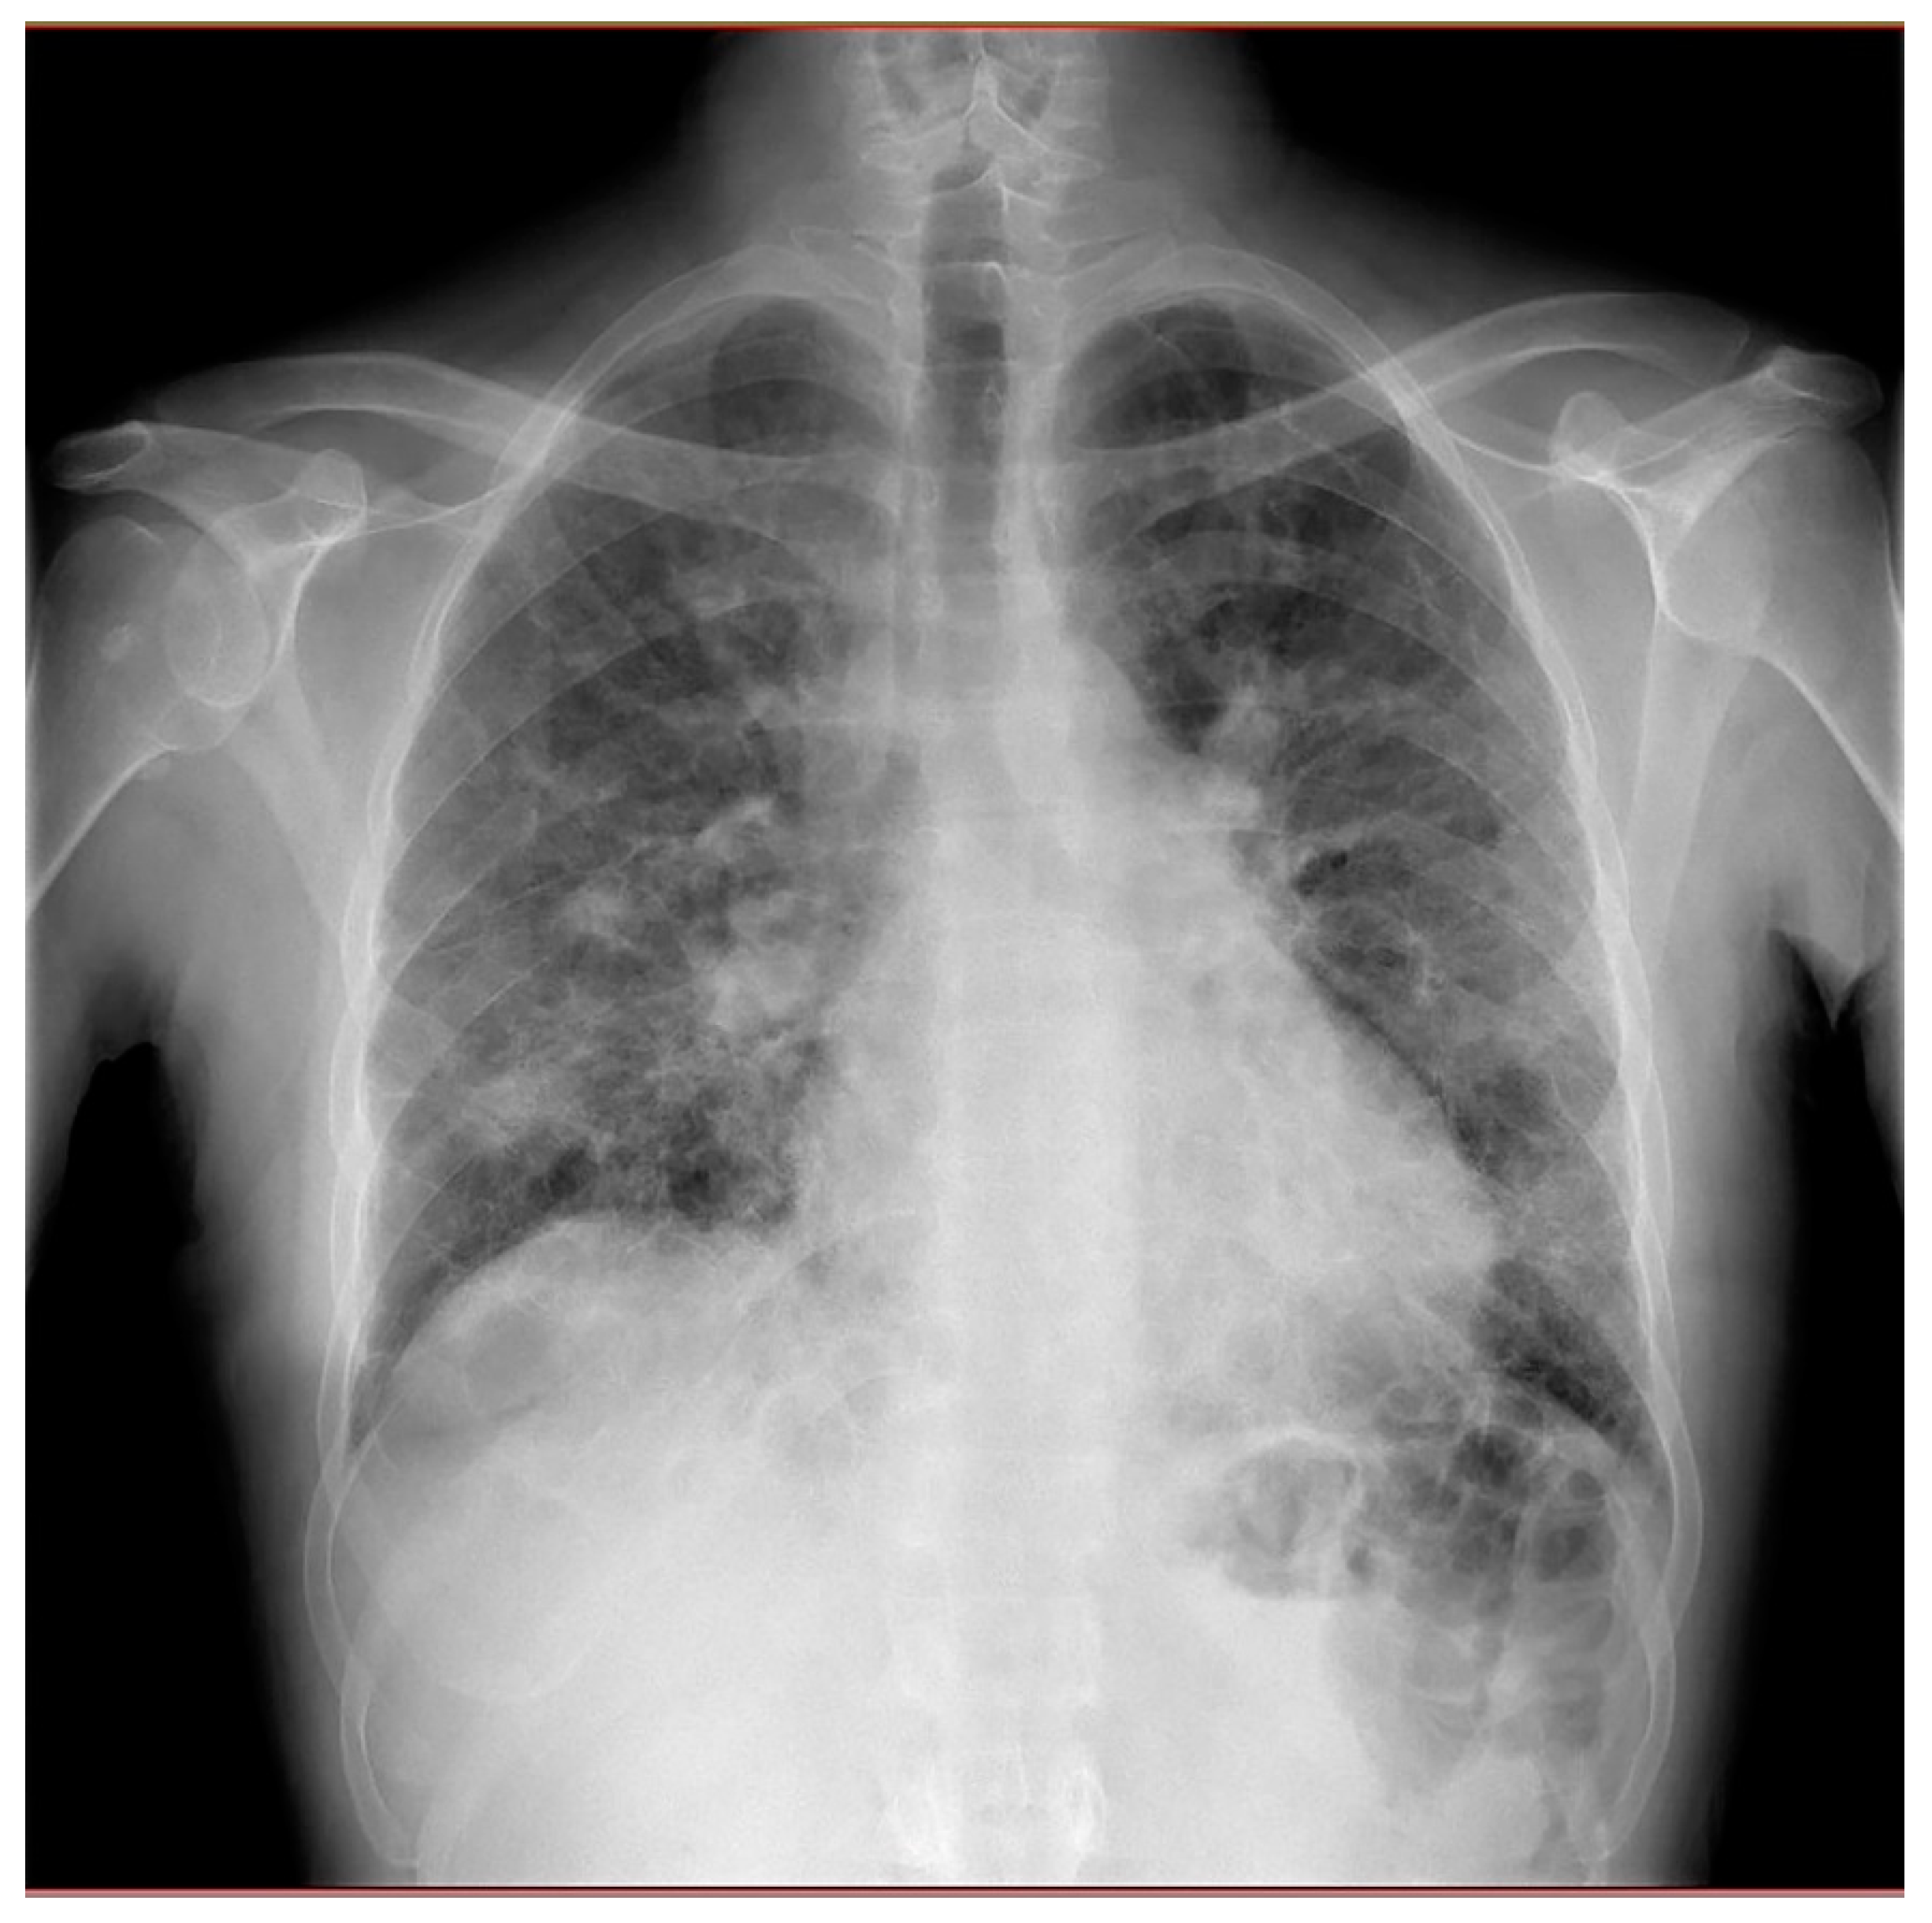

Chest X-rays showed diffuse fibrosing interstitial lung disease with multiple, bilateral parenchymal opacities, with no clear evidence of inflammatory foci (Figure 2).

Figure 2. Chest X-rays revealing diffuse fibrosing interstitial lung disease with multiple, bilateral parenchymal opacities, with no clear evidence of inflammatory foci.